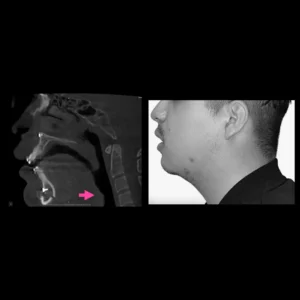

Hiperplasias o hipoplasias condilares

Es una enfermedad rara que se considera un crecimiento patológico y progresivo de uno o ambos cóndilos mandibulares, cuanto más grave es la patología, mayor asimetría y maloclusión desarrolla, que no solo afecta al desarrollo, masticación, deglución, habla, etc. si no que además esta particular entidad afecta altamente al individuo en un nivel psicosocial.